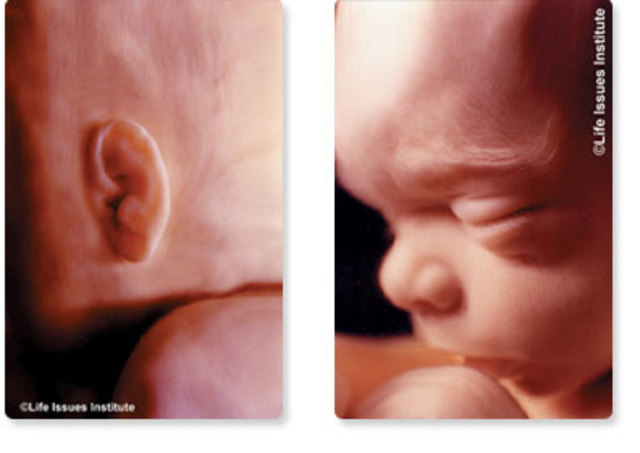

• 12 Semana de Gestación

12 Semana de Gestación

En los rasgos externos la cabeza está erecta, el cuello está casi recto y bien definido, también el oído externo adopta su forma y se ha desplazado casi a su posición definitiva en la cabeza

• Period: to

12 SDG

El saco vitelino se ha retraído, el feto deglute líquido amniótico y puede responder a la estimulación de la piel, los ovarios descienden por debajo del reborde pélvico, también se produce la hormona paratiroidea y la sangre se puede coagular